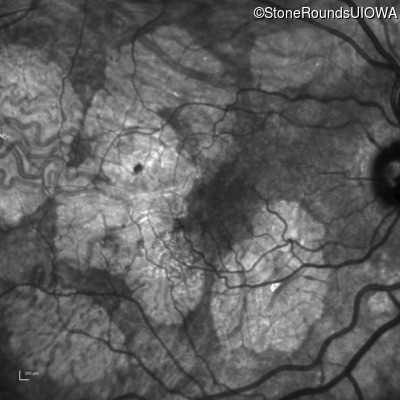

Diagnosis & molecular findings

Disease Gene Allele 1 variant(s) Allele 2 variant(s) Inheritance mode

AR Stargardt Disease ABCA4 Gly1507Arg GGG>AGG IVS42+1 G>A AR